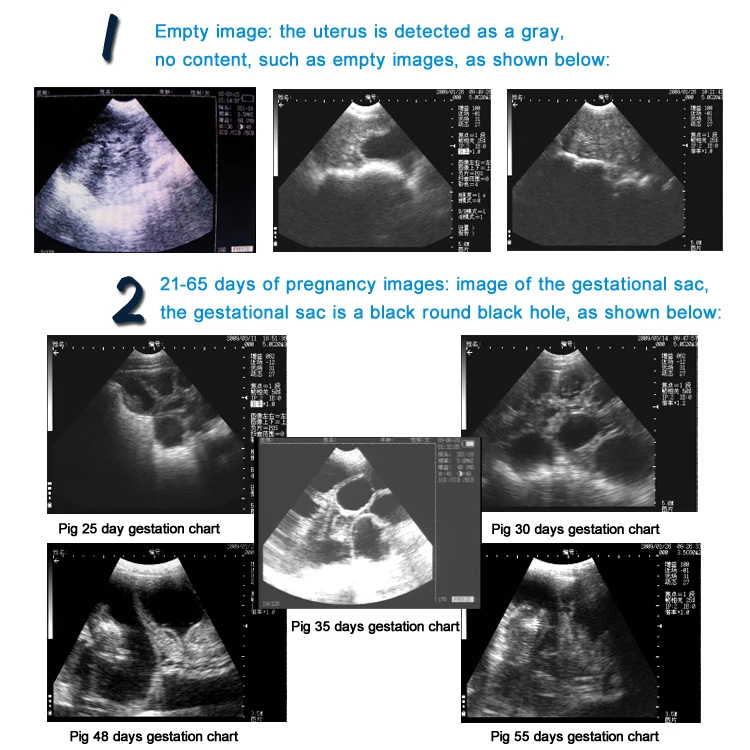

5,6 дюймовый Ветеринарный ультразвуковой сканер для домашнего скота портативный для крупного рогатого скота корова свинья овца лошадь ферма ультразвуковое оборудование для беременности

TC-210 Ветеринарный ультразвуковой сканер, используемый в животноводческих фермах и животноводческих клиниках. 3,5 МГц механический вентилятор развертки зонд подходит для свиней, овец и домашних животных.